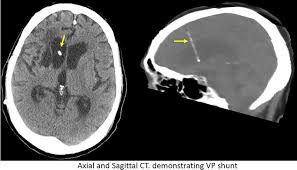

Axial And Sagittal Ct Demonstrating Ventriculoperitoneal Vp Shunt Download Scientific Diagram